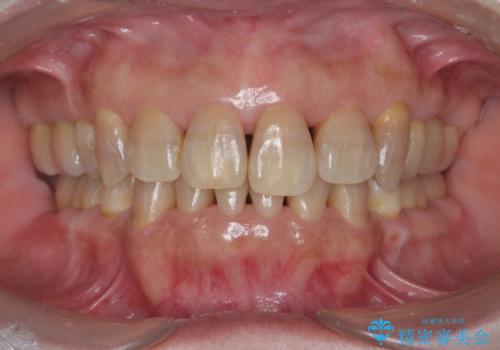

[メタルフリー] 虫歯・銀歯だらけの口腔内を全顎治療

![[メタルフリー] 虫歯・銀歯だらけの口腔内を全顎治療の症例 治療後](https://seimitsushinbi.jp/wp/wp-content/uploads/2025/03/530cf6cca6451bc106a9fb69dd58908a-500x350.jpg?v=1741918343)